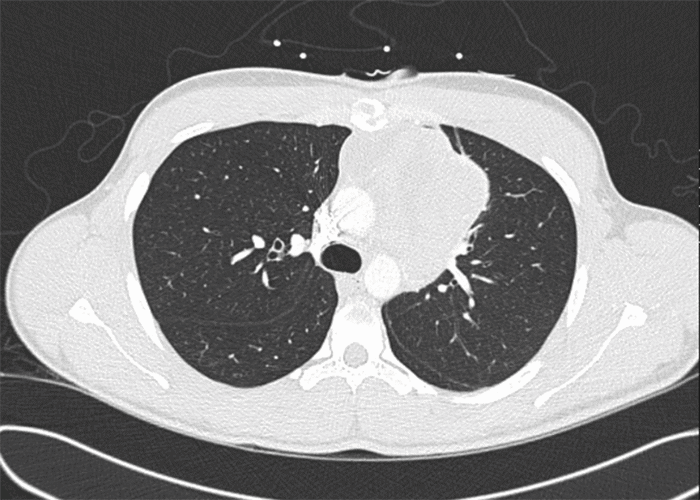

A 20-year-old male presented with dyspnea and chest pain that radiated to the left shoulder and back. He denied fever, cough, nausea, vomiting, night sweats, or weight loss and reported no tobacco or environmental exposures. Laboratory values were all within normal limits apart from an elevated alkaline phosphatase (172 IU/L, normal: 20-140 IU/L). Alpha-fetoprotein marker was found to be 1.20 ng/mL (normal: <10 ng/mL), lactate dehydrogenase (LDH) was found to be 142 U/L (normal: 140-280), and beta-human chorionic gonadotropin (ß-hCG) was negative. Plain radiograph (Figure 1) was significant for a left paratracheal lobulated mediastinal mass causing right tracheal deviation. Chest computed tomography (CT) revealed a large anterior mediastinal mass measuring 8.5 × 8.3 × 7.2 cm (Figure 2 and Figure 3). Scrotal ultrasound revealed no masses, though nonspecific scattered bilateral testicular microcalcifications were noted. A CT-guided biopsy of the mass was performed however was non-diagnostic. Due to a high index of suspicion for malignancy, an incisional biopsy via Chamberlain procedure was performed.

Figure 2. Axial CT Image with Large Heterogeneous Anterior Mediastinal Mass. Published with Permission

Pulmonary nodules 11.0 × 9.0 mm left posterior apical juxtapleural, 2.0 mm left anterior upper lobe, and 3.0 mm subpleural left lower lobe were also noted